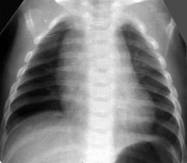

Снижение пневматизации легких, воздушные бронхограммы, границы сердца на рентгенограмме ещё различимы (Рис.5).

Рисунок 5. РДС. Рентгенограмма в прямой проекции, в горизонтальном положении. Верхние доли легких и средняя доля справа неоднородно слабоинтенсивно затемнены, корни легких расширены, не структурны. Сосудисто-интерстициальный рисунок легких деформирован, усилен, размыт. Тень средостения с нечётким контуром, протекционно смещена влево за счёт подворота. (Диагностика и лечение РДС недоношенных // метод. рекомендация, 2007)